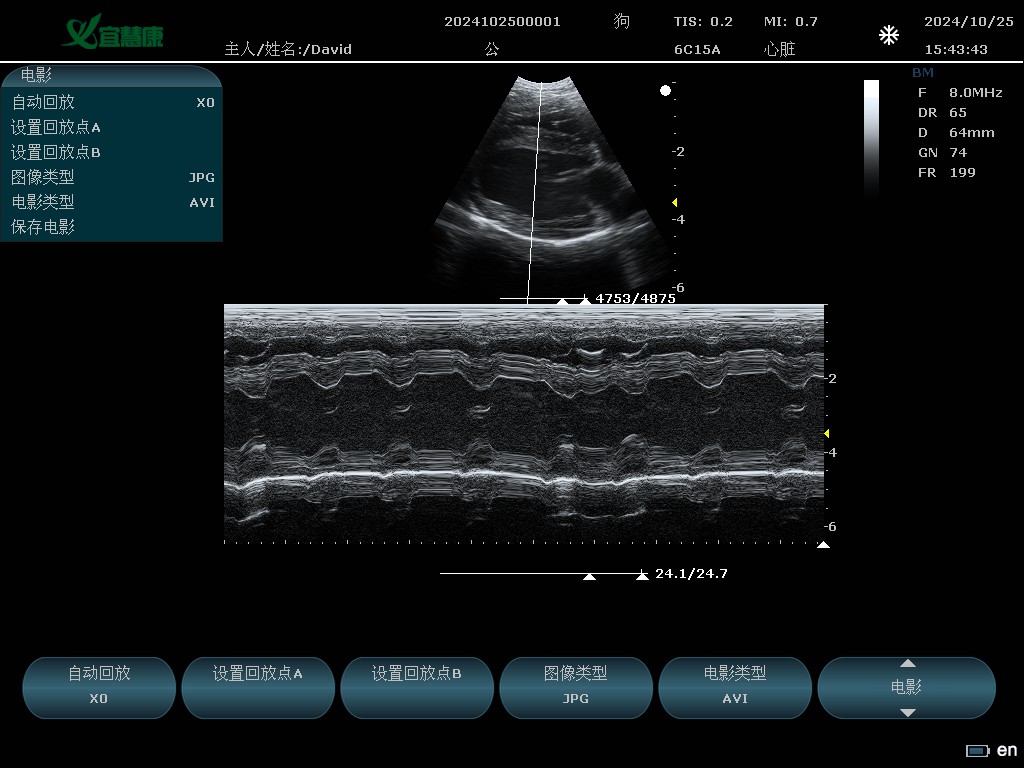

YHK-C90可以用于动物腹部、心脏、产科、小器官、血管、肌腱等方面的检查。支持的动物类型有猫、狗、牛、马、羊 其他。

6C15A: 6.5MHz/R15/80阵元微凸探头;

M模式

B、双幅、四幅、B+M、M、B+Color、B+PW、PW、B+Color+PW、★B/BC双实时

时间线模式(M, PW), 最大:≥ 190s

心脏B、M、PW模式应用测量

扫描速度:0-4

焦点位置:0-15

动态范围:30-165 5档可调